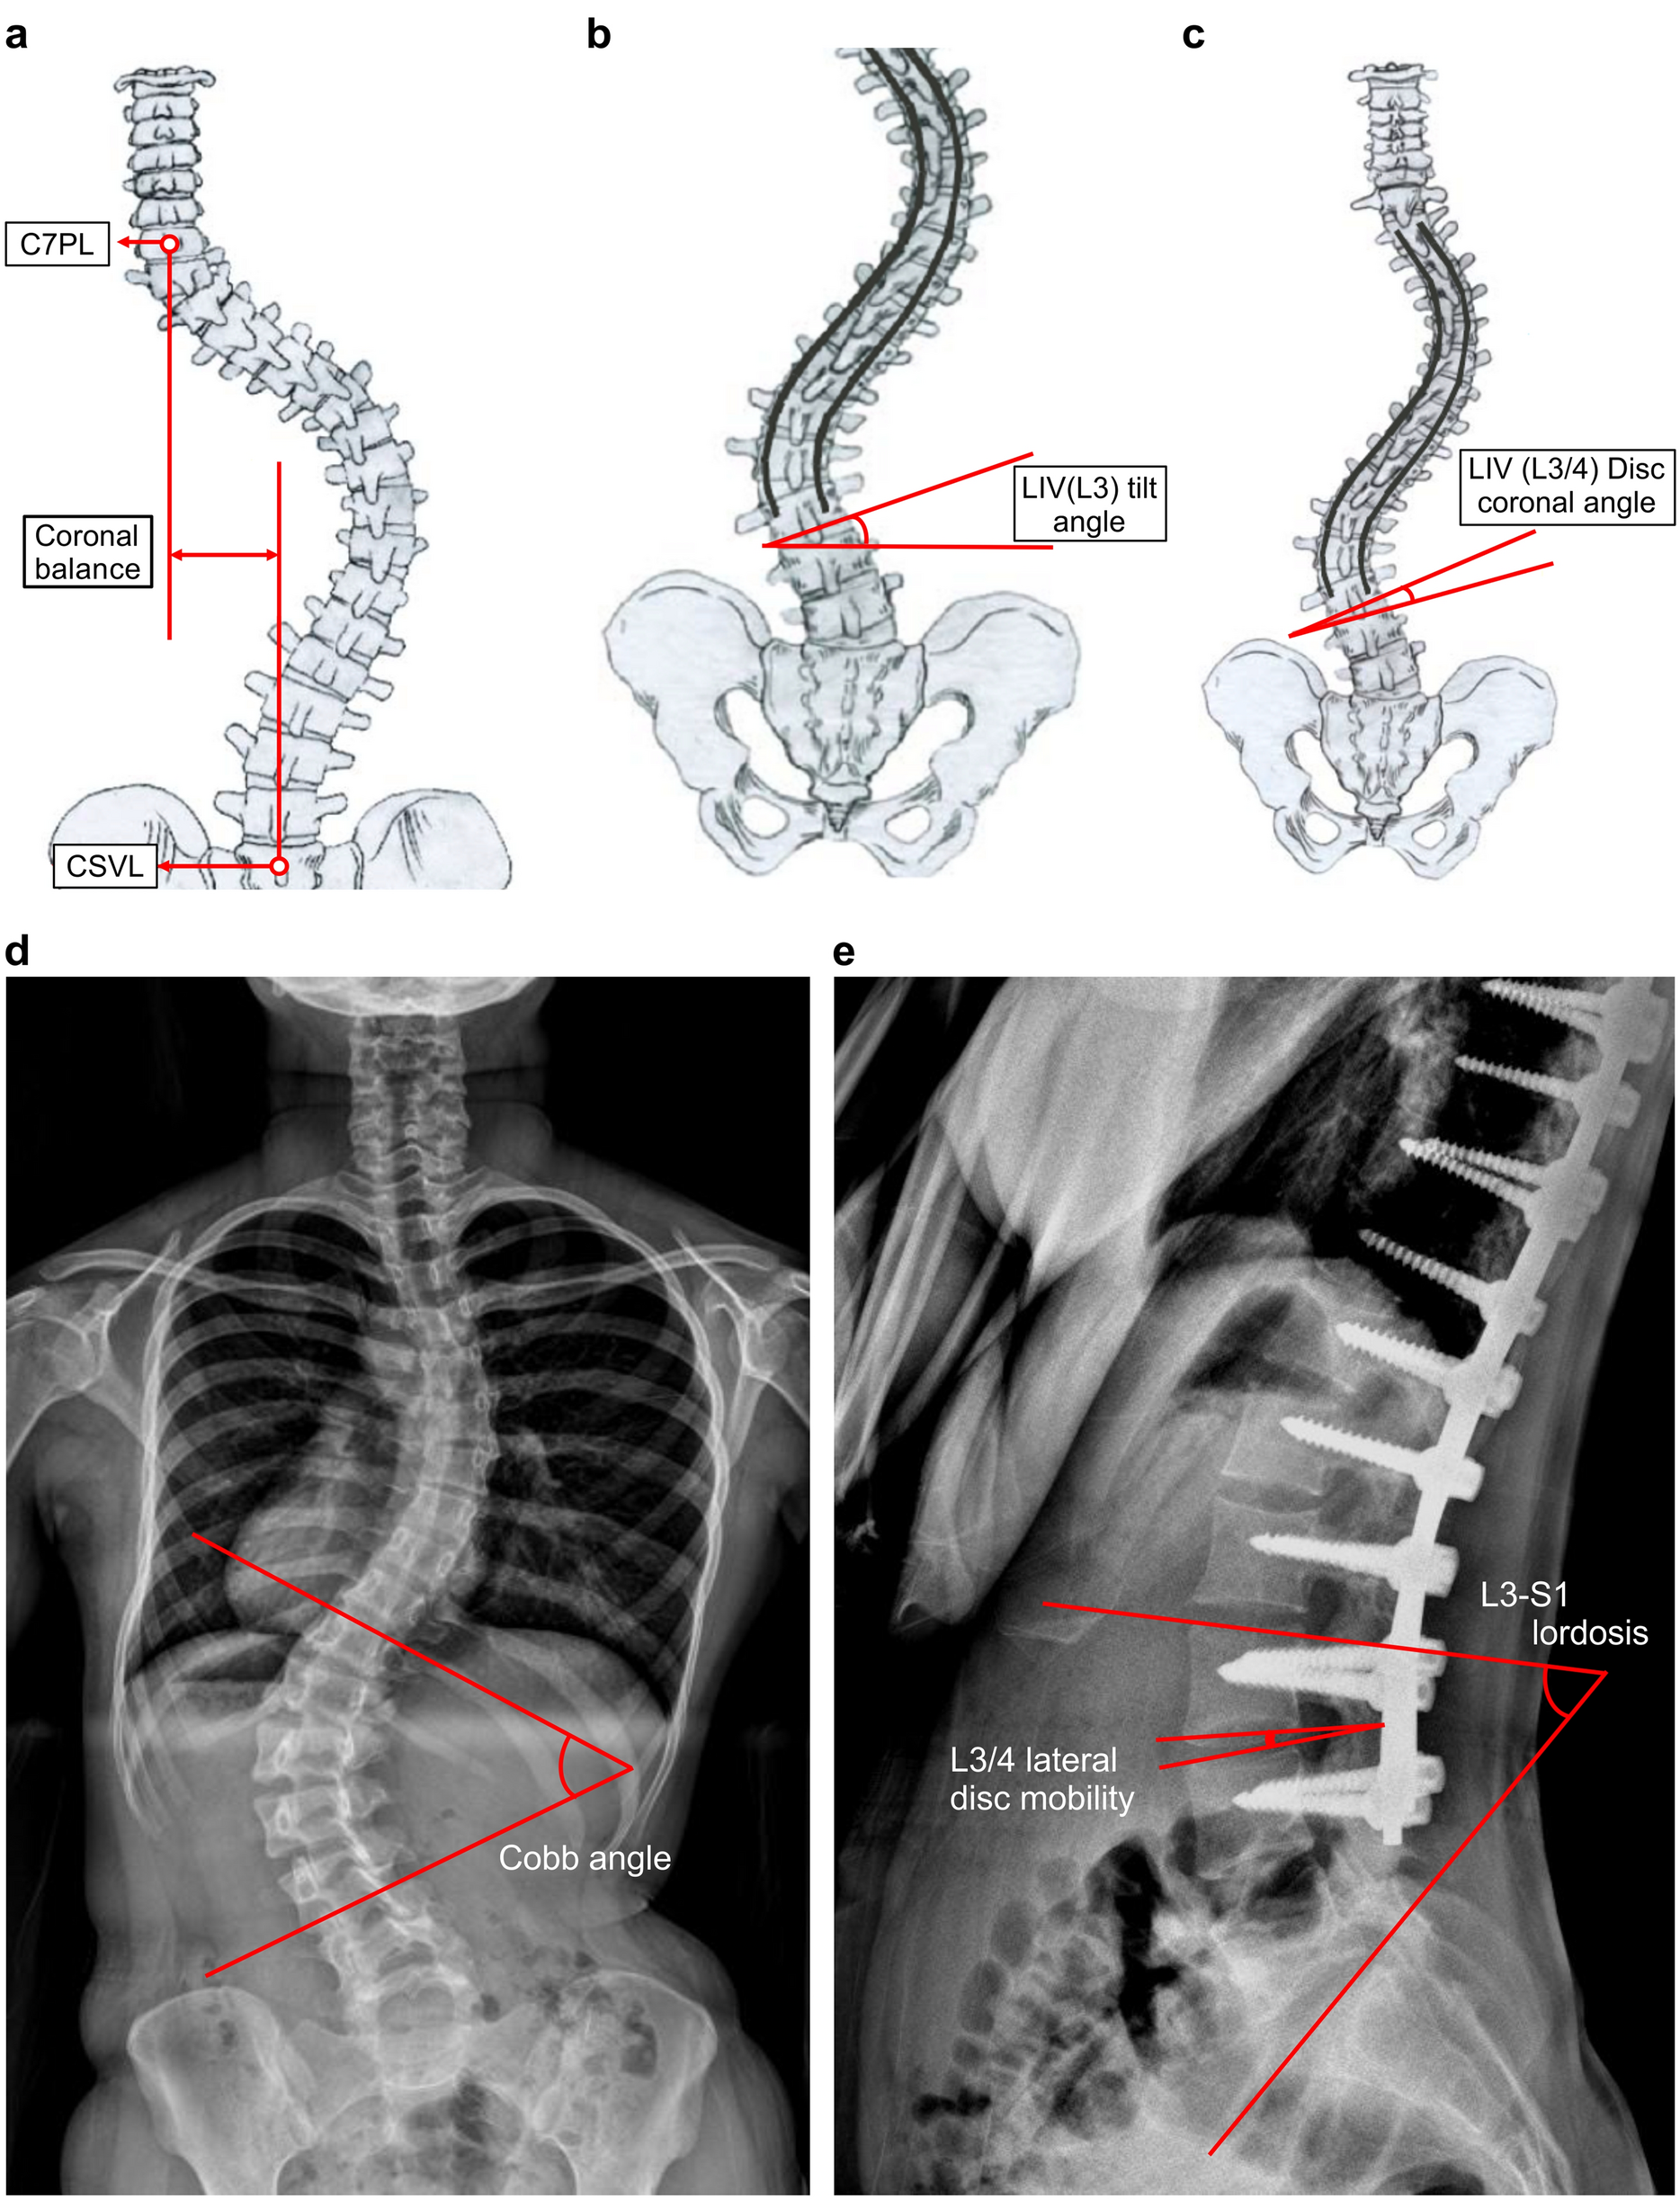

Figure 2

Radiographic parameters measured in the standing whole spine PA, lateral images, and full flexion–extension dynamogram of lumbar spine (a) Coronal balance is the distance (mm) between the coronal C7 plumb line and the CSVL. (b) The LIV (L3) tilting angle is the angle between the line measured on the inferior endplate of L3 and the horizontal line. (c) The LIV (L3/4) disc coronal angle was measured from lines between the L3 lower endplate and the L4 upper endplate. (d) The Cobb angle is the angle between the upper and lower end vertebra. (e) L3-S1 lordosis is indicated as the line measured on the superior endplate of the L3 and S1 regions. The L3/4 lateral disc mobility is the angle range of the L3/4 disc in full flexion–extension dynamogram.